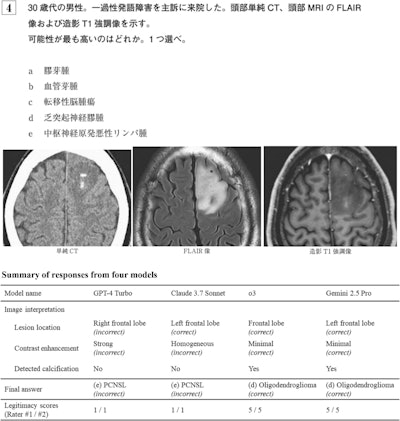

Question 4 from the Japan Diagnostic Radiology Board Examination 2024, representing a clinical scenario of a man in his 30s presented with transient dysphasia. The question asks to identify the most probable diagnosis from the following options: (a) glioblastoma, (b) hemangioblastoma, (c) metastatic brain tumor, (d) oligodendroglioma, and (e) primary central nervous system lymphoma (PCNSL). The correct answer is (d) oligodendroglioma. The figure also includes a summary of responses from four large language models, along with their legitimacy scores rated by diagnostic radiologists.Question 4 from the Japan Diagnostic Radiology Board Examination 2024, representing a clinical scenario of a man in his 30s presented with transient dysphasia. The question asks to identify the most probable diagnosis from the following options:  (a) glioblastoma, (b) hemangioblastoma, (c) metastatic brain tumor, (d) oligodendroglioma, and (e) primary central nervous system lymphoma (PCNSL). The correct answer is (d) oligodendroglioma. The figure also includes a summary of responses from four large language models, along with their legitimacy scores rated by diagnostic radiologists.Japanese Journal of Radiology